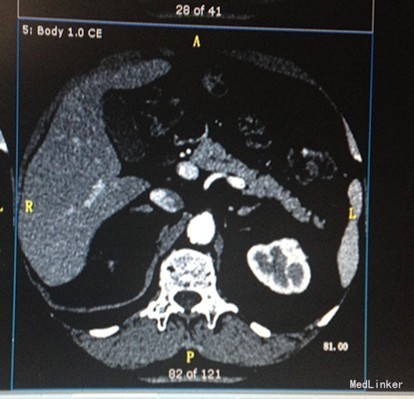

入院查体: BMI:25.39Kg/m2,右下肢活动受限,肌力正常,无畸形,无关节痛,右下肢麻木。 辅助检查:腹部超声:脂肪肝超声所见前列腺内结石或钙化。肾上腺CT:双侧肾上腺占位,请结合临床。左肾囊肿。血脂分析:TG 3.46mmol/L,TC 5.90mmol/L,LDL-C 4.06mmol/L。OGTT及胰岛功能试验未见明显异常。24小时动态心电图:窦性心律/偶发房性早搏、成对房性早搏、短阵房性心动过速/偶发室性早搏、多源室性早搏/ST-T段改变。24小时动态血压:平均血压134/90mmHg,昼夜血压节律异常(非杓型),昼夜血压负荷升高 肾上腺皮质激素系列: 8:00 15:00 24:00 ACTH 15.50 15.45 3.59 COR 386.6 298.1 166.20 肾上腺皮质醇节律及小剂量地塞米松试验 8:00 15:00 24:00 7:00 7:15 ACTH 36.08 14.7 9.08 15.7 17.62 COR 514 284.5 113.5 356 313.3 抑制率:34% 小剂量地塞米松抑制试验(标准法) 8:00 7:00 7:15 COR 241.1 27.17 18.32 ACTH 20.79 2.77 2.49 醛固酮立卧位:(第1、2套) 卧位 立位 卧位 立位 醛固酮 0.11 0.18 0.16 0.17 PRA 0.04 3.2 0.58 5.5 比值 275 5 27 3 醛固酮立卧位(第三套) 卧位 立位 醛固酮 0.14 0.14 PRA 1.4 6.8 比值 10 2.05 卡托普利试验抑制试验: 给药前 1小时 2小时 醛固酮 0.15 0.14 0.14 PRA 9.1 5.6 6.2 比值 116 93 81 试验结果提示未被抑制

诊断:双侧肾上腺占位;高血压;血脂异常症 治疗:拜新同降压,立普妥降脂

住院期间对症给予拜新同控制血压,监测24小时控制血压结果基本正常,后多次院内监测血压结果波动于125-145/80-95mmHg,监测3次血离子血钾均在正常范围,完善各功能试验,虽卡托普利试验未被抑制,但诊断功能性肾上腺肿物证据不足。